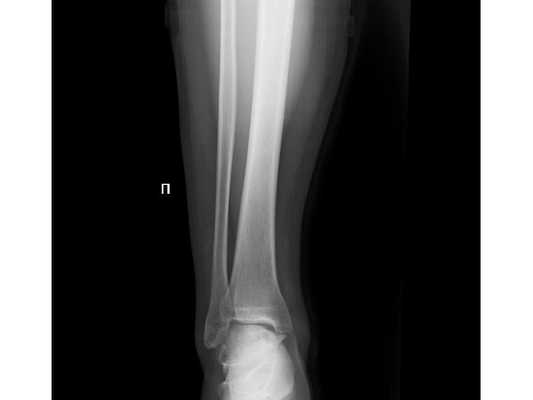

При осмотре определяется отёк мягких тканей области голеностопного сустава. Геометрия сустава изменена. Движения в голеностопном суставе ограничены болями, при пальпации пациент отмечает боли в этой области. Также при пальпации есть болезненность в верхней трети правой голени в проекции головки малоберцовой кости.

- Рентгенография правого голеностопного сустава в двух проекциях.

- Рентгенография правой голени на протяжении с захватом коленного и голеностопного суставов.

Закрытый оскольчатый перелом внутренней лодыжки правой голени со смещением отломков. Закрытый перелом верхней трети малоберцовой кости правой голени. Повреждение дистального межберцового синдесмоза ( соединения большеберцовой и малоберцовой костей) . Подвывих стопы кнаружи (Maisonneuve-type fracture).